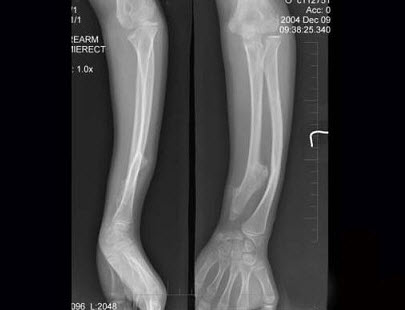

56、单项选择题

12岁女性患者,左前臂外翻畸形4年,摄片如图所示,最佳的诊断是()